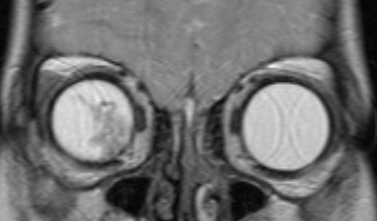

- D - рассеянные опухоли с крупными опухолевыми массами, разнокалиберными отсевами в стекловидном теле и/или субретинальном пространстве в более чем 3 мм от новообразования с субретинальной жидкостью более 6 мм от образования, включая полную отслойку сетчатки (рис. 3 и 4).

![Визуализация ретинобластомы с помощью МРТ. Размеры образования соответствуют клинической группе D]()

Рис. 3. Визуализация ретинобластомы с помощью МРТ. Размеры образования соответствуют клинической группе D

![Визуализация ретинобластомы с помощью МРТ. Фронтальное изображение орбит. Клиническая группа D]()

Рис. 4. Визуализация ретинобластомы с помощью МРТ. Фронтальное изображение орбит. Клиническая группа D